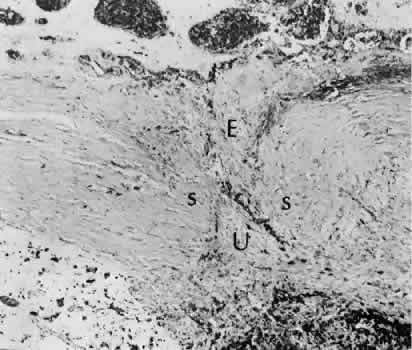

Fig. 8. Following a scleral incision, granulation tissue from episcleral tissue (E) and uveal tissue (U) will proliferate through the full extent of the sclera. The tissue will remodel along tension lines to reapproximate the tensile strength of the original tissue (Hematoxylin-eosin stain; × 28.)